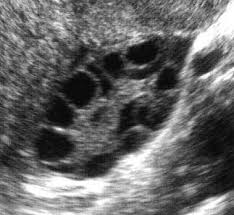

- Hình ảnh buồng trứng đa nang trên siêu âm

+ Hai buồng trứng to

+ Có trên 10 nang (<10mm) ở mặt phẳng khảo sát, hình chuỗi hạt.

+ Mô đệm dầy và sáng